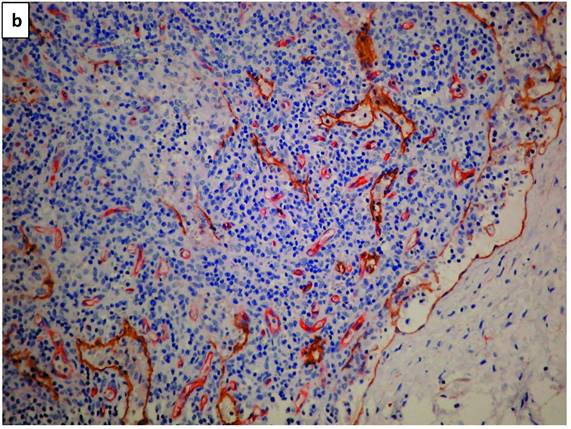

Lymphatic vessels stained brown with D2-40 (podoplanin) (Figure 1a). A double staining highlighted blood vessels in pink-red (CD34 with AEC substrate) and lymphatic vessels in brown (D2-40 with DAB substrate - Figure 1b). Scarce HRS cells did not demonstrate a specific configuration relationship with lymphatic vessels (Figure 1c).

a. The photomicrograph of a classical Hodgkin lymphoma section, highlights predominant lymphatic vessels stained with anti-D2-40 (Podoplanin) in brown (IHC X340 with DAB substrate). b. Double staining of a section of classical lymphoma: blood vessels stain in pink-red with CD34 and lymphatic vessels in brown with D2-40. Note a residual subcapsular sinus on the right margin is highlighted in brown (IHCX340 with AEC for blood vessels and DAB for lymphatic vessels). c. Double staining of a section of classical lymphoma: blood vessels stain pink with CD34 and lymphatic vessels stain brown with D2-40. Note scarce Hodgkin (mononuclear) tumor cells (arrows) show no space association with lymphatic vessels (IHCX340).

Figure 1b, with its opened subcapsular sinus, is the nearest to a reactive lymph node, as the involvement with cHL is partial. The lymph vessels distribution is therefore variable.